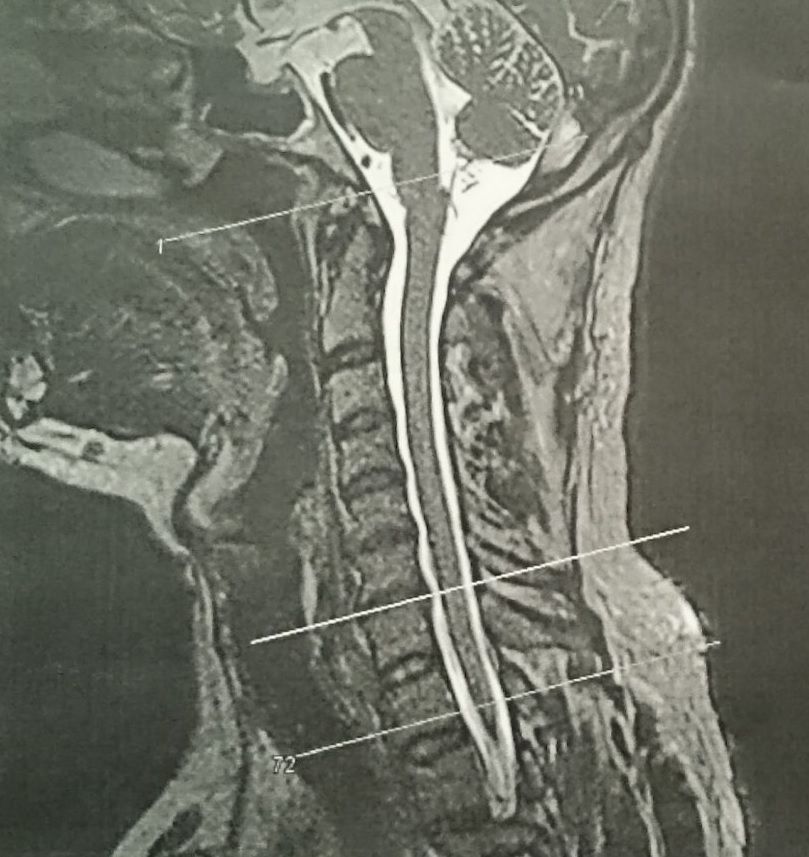

Und da ist auch ein nicht unerheblicher Grund, bei so einem Klunker-Sofa ganz kleinlaut Ja! zu sagen: Ein klitzekleines Problemchen bei C6/C7 (wers schon kennt/andere dürfen sich drauf freuen bzw. man zähle einfach 6 Wirbel von oben) an die kürzlich in so einer perfekt ausgeleuchteten Stanley Kubrick-Röhre eine laaange Kanüle gesetzt wurde. Örtliche Betäubung only.